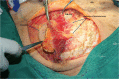

The role of the pectoralis major myocutaneous flap (PMMF) in head and neck reconstruction is challenged recently due to its natural drawbacks and the popularity of free flaps. This study was designed to evaluate the indications and reliability of using a PMMF in the current free flap era based on a single center experience. The PMMF was harvested as a pedicle-skeletonized flap, with its skin paddle caudally and medially to the areola, including the third intercostal perforator, preserving the upper one third of the pectoralis major muscle. The harvested flap was passed via a submuscular tunnel over the clavicle. One hundred eighteen PMMFs were used in 114 patients, of which 76 were high-risk candidates for a free flap; 8 patients underwent total glossectomy, and 30 underwent salvage or emergency reconstruction. Major complications occurred in 4 patients and minor complications developed in 10. Tracheal extubation was possible in all cases, while oral intake was possible in all but 1 case. These techniques used in harvesting a PMMF significantly overcome its natural pitfalls. PMMFs can safely be used in head and neck cancer patients who need salvage reconstruction, who are high risk for free flaps, and who need large volume soft-tissue flaps.